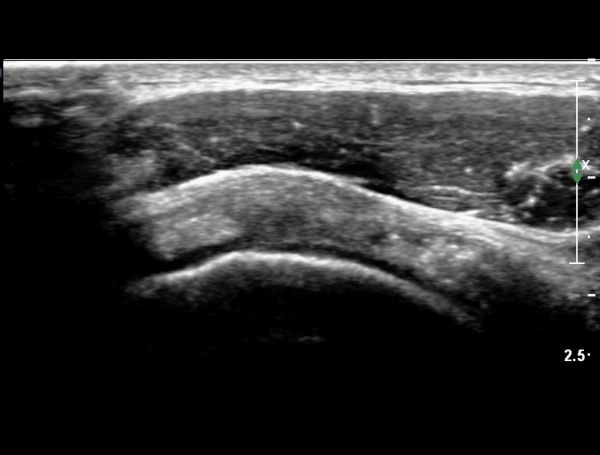

°ß°©ÇÏ±Ù°Ç È¾´Ü¸é°Ë»ç¿¡¼­ °Ç »óºÎ¿¡ ÀÌÁúÀûÀÎ ¿¡ÄÚ¸¦ º¸¿© °ß°©ÇÏ±Ù°Ç »óºÎ ºÎºÐÆÄ¿­ÀÌÃßÁ¤µÈ´Ù(»çÁø 5, 6, 7)